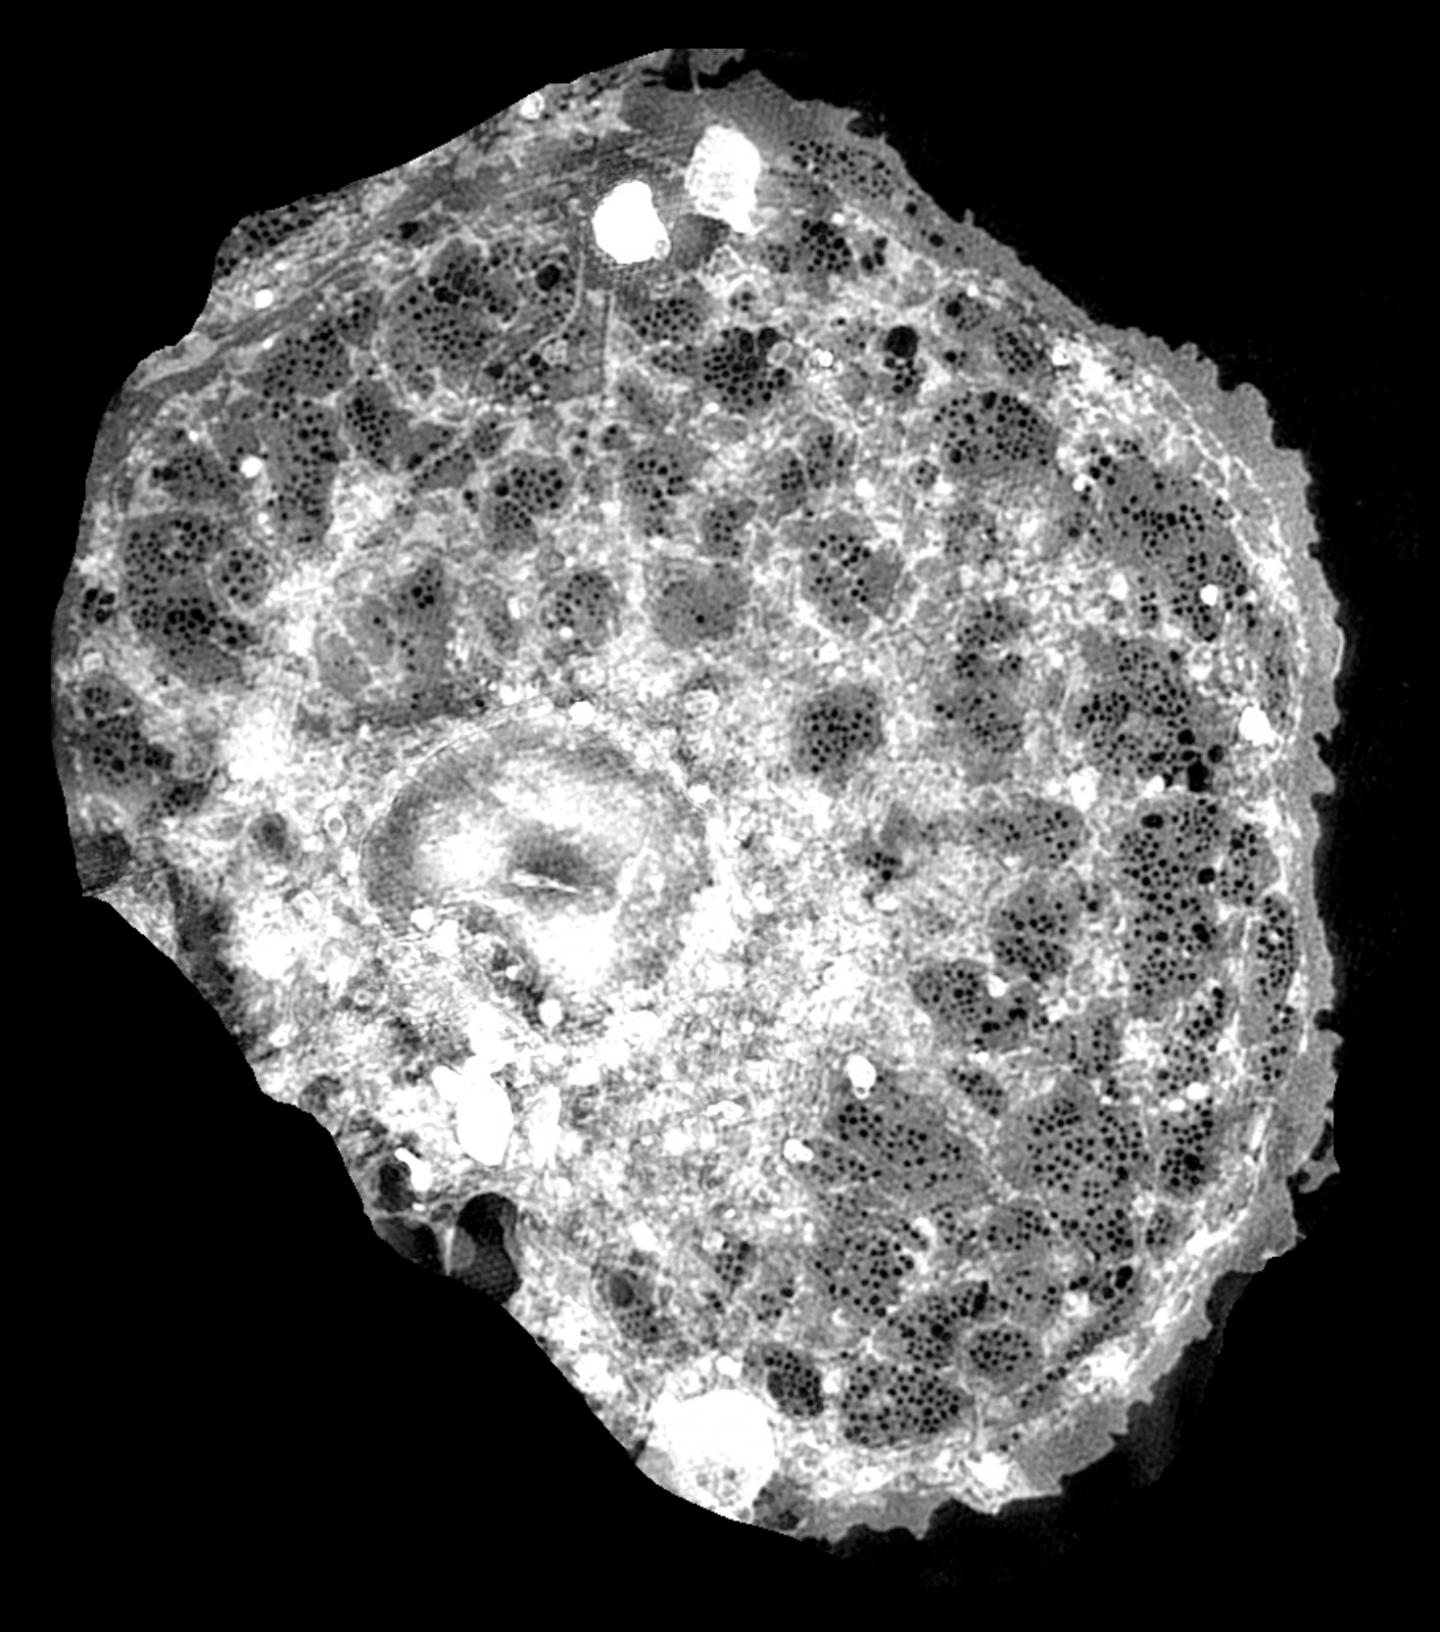

The young scientists will be carrying out research for their doctorates at six European partner universities and at companies in a total of nine countries. The procedures to be developed in the project should be minimally invasive. As in endoscopy, new optical instruments will be developed and applied to study liver samples with high-resolution microscopy. In the long term, the methods should also be used to carry out microscopic examinations of liver cells directly in the body.

Huser's research group 'Biomolecular Photonics' is developing high-resolution microscopes that can make structures in body cells visible and accessible to research that traditional optical microscopes are unable to show.